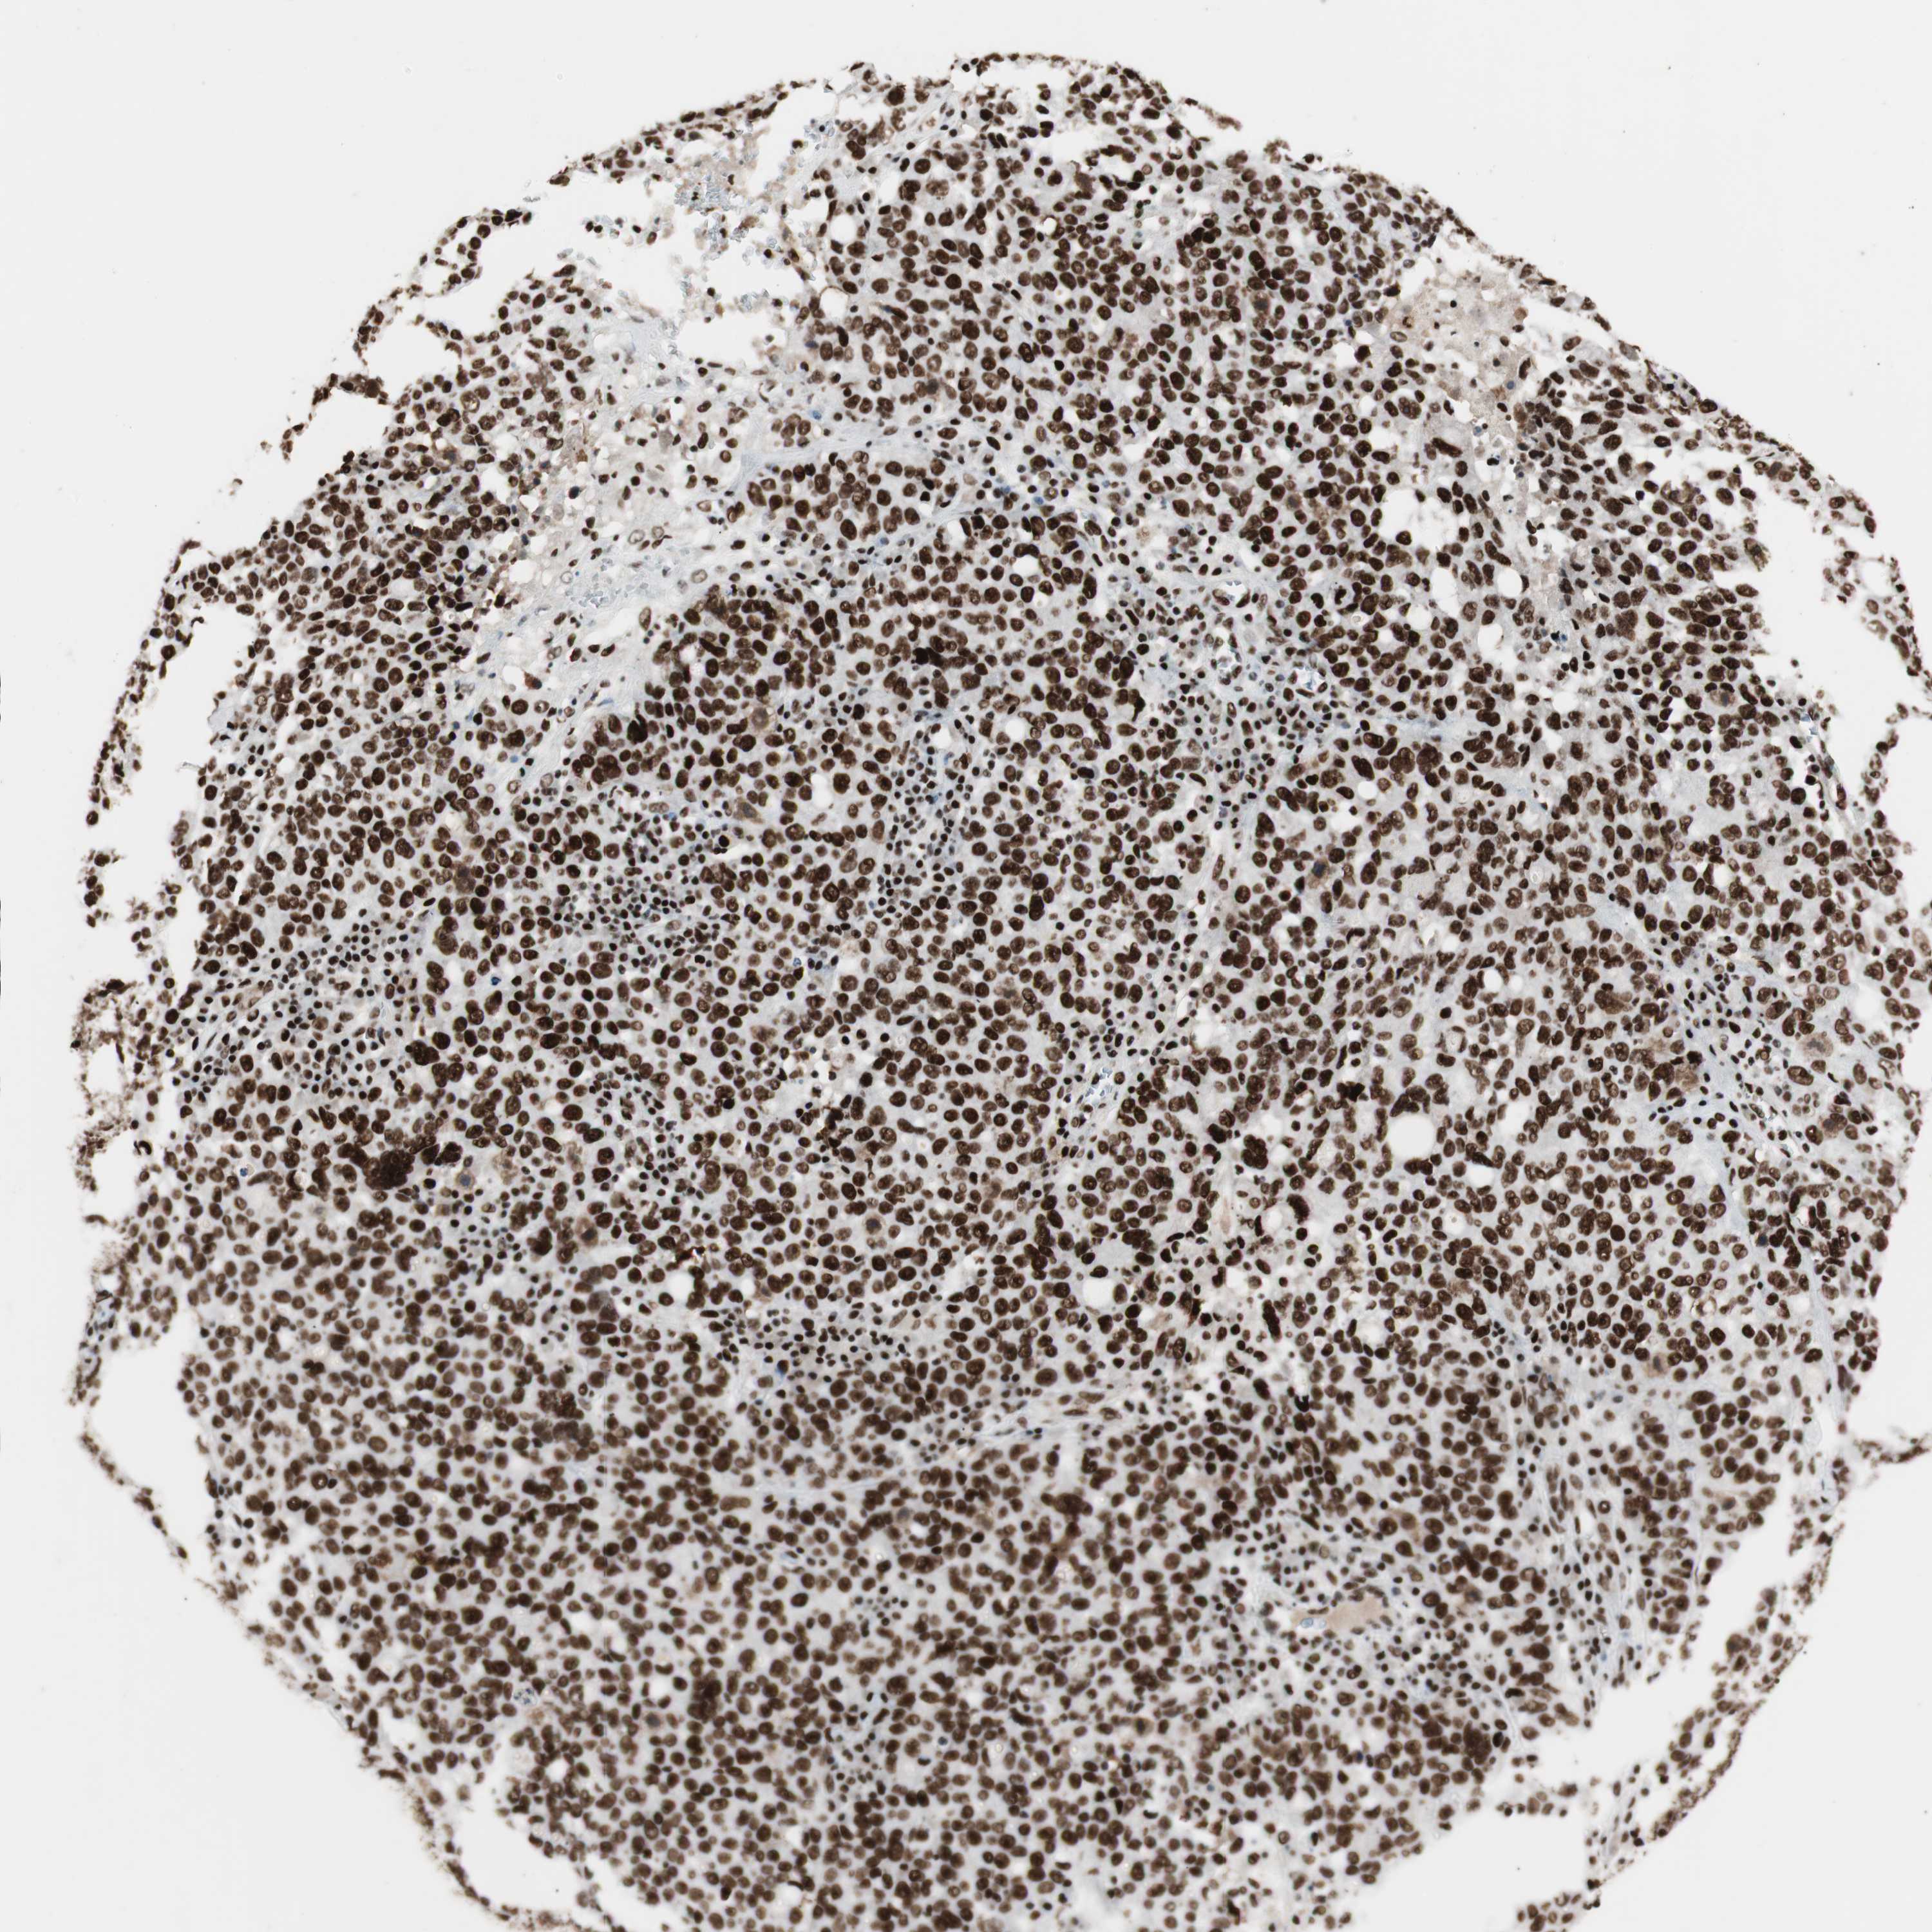

OVARIAN CANCER - Protein expressioni

A mouse-over function shows sample information and annotation data. Click on an image to view it in a full screen mode. Samples can be filtered based on level of antibody staining by selecting one or several of the following categories: high, medium, low and not detected. The assay and annotation is described here.

Note that samples used for immunohistochemistry by the Human Protein Atlas do not correspond to samples in the TCGA dataset.

Antibody stainingi

Antibody staining in the annotated cell types in the current human tissue is reported as not detected, low, medium, or high, based on conventional immunohistochemistry profiling in selected tissues. This score is based on the combination of the staining intensity and fraction of stained cells.

Each image is clickable and will lead to virtual microscopy that enables deeper exploration of all samples and also displays staining intensity scores, fraction scores and subcellular localization as well as patient and tissue information for each sample.

Antibody HPA012510

Antibody CAB008388

Cystadenocarcinoma, serous, NOS

Carcinoma, NOS